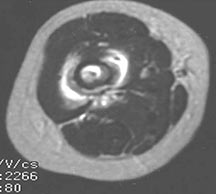

- May arise from any bone and any site within a bone (epiphyseal, metaphyseal, diaphyseal)

- Radiographically variable appearance: may appear benign (geographic) or malignant (permeative or moth eaten)

Radiographic Presentation